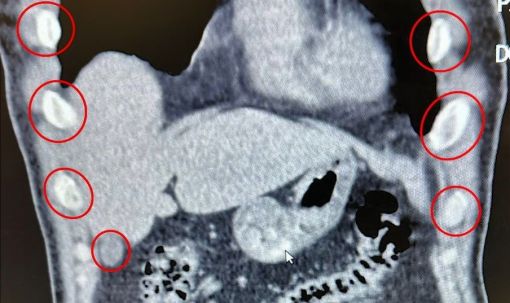

Tatvan ilçesinde durdurulan bir otobüste yolcu olarak seyahat eden yabancı uyruklu 2 şahıs gözaltına alındı. Şahısların yapılan tıbbi müdahalesinde, yuttukları 136 kapsül halinde toplam 1 kilo 48 gram metamfetamin uyuşturucu madde ele geçirildi.